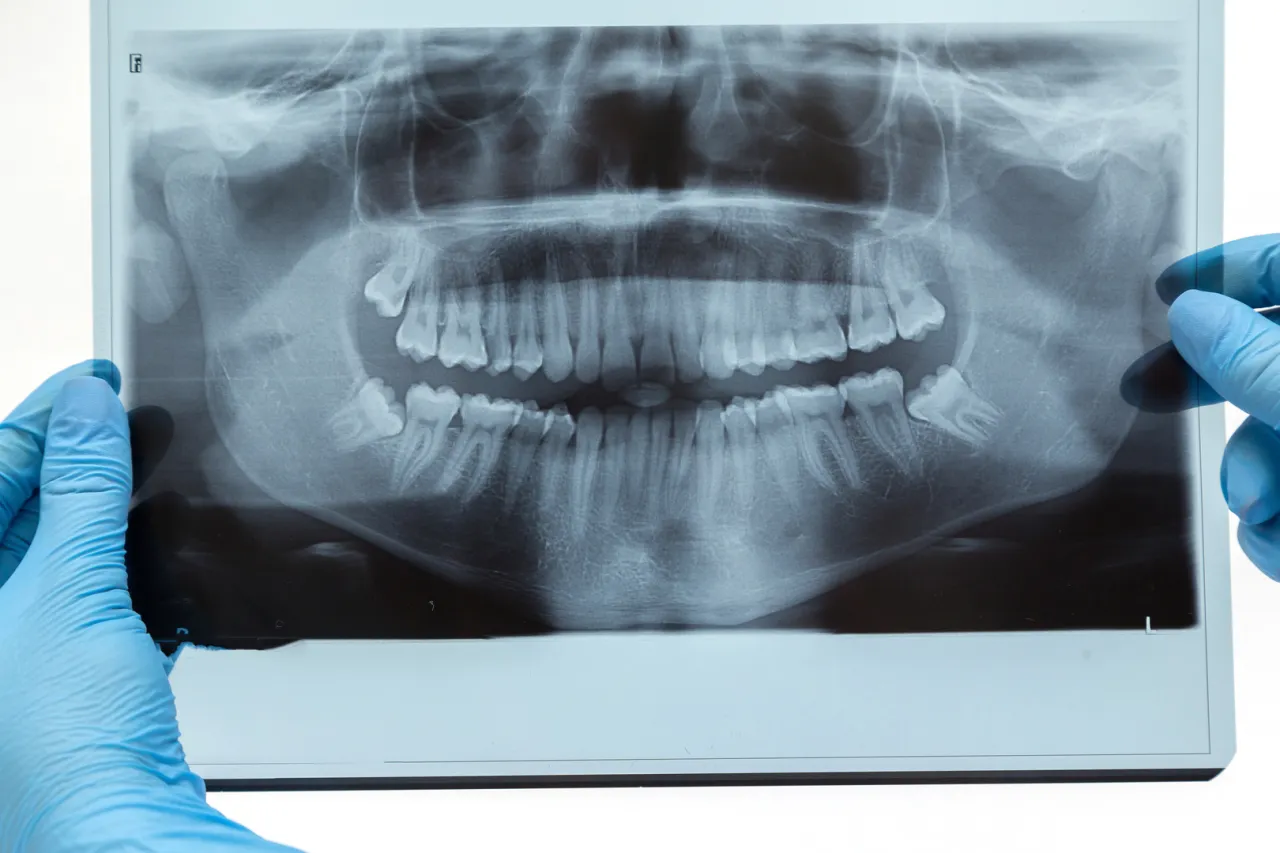

Przed samym zabiegiem zawsze odbywa się konsultacja u chirurga stomatologa. Jest to ostatni, ale niezwykle ważny etap kwalifikacji. Podczas tej wizyty chirurg dokładnie oceni stan Twojego zęba i całej jamy ustnej. Omówi z Tobą szczegółowy plan zabiegu, wyjaśni możliwe ryzyka i odpowie na wszystkie Twoje pytania. To doskonała okazja, aby rozwiać wszelkie wątpliwości. Często na tym etapie wykonuje się lub analizuje zdjęcie pantomograficzne, które jest kluczowe dla precyzyjnego zaplanowania ekstrakcji.

Czy zdjęcie pantomograficzne jest zawsze w cenie?

Zdjęcie pantomograficzne, czyli panoramiczny rentgen zębów, jest niezwykle ważnym badaniem diagnostycznym przed usunięciem ósemki. Pozwala chirurgowi ocenić położenie zęba, jego korzenie oraz relacje z sąsiednimi strukturami, takimi jak nerwy. Dobra wiadomość jest taka, że zdjęcie pantomograficzne jest refundowane przez NFZ, ale tylko wtedy, gdy jest wykonywane w ramach przygotowania do zabiegu chirurgicznego usunięcia ósemki. Oznacza to, że jeśli lekarz uzna je za niezbędne do prawidłowego zaplanowania ekstrakcji, nie poniesiesz za nie dodatkowych kosztów. Jeśli jednak wykonasz je prywatnie, bez skierowania na zabieg NFZ, będziesz musiał pokryć jego koszt.